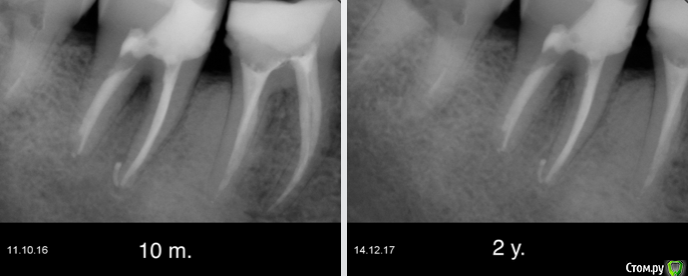

Гарриевич Опубликовано 22 декабря, 2017 Поделиться Опубликовано 22 декабря, 2017 (изменено) админы, если уже создавал такую тему, объедините пожалуйста абсолютно бессимптомный зуб, пациента ничего не беспокоило кроме... да нет, вообще ничего не беспокоило. Лечение в два посещения через гидроксид кальция. Обтурация инжектором. Будут вопросы спрашивайте, каких то еще особенностей сразу не вспомню PS сроки наблюдения 10 месяцев и два года Изменено 22 декабря, 2017 пользователем Гарриевич 8 Ссылка на комментарий

Гарриевич Опубликовано 23 декабря, 2017 Автор Поделиться Опубликовано 23 декабря, 2017 Скорее всего гутту съехала пока снимки делали. Вложения гидроокиси на 2 недели. В данном случае порошок чистого гидроксида кальция замешанный с водой непосредственно перед внесением. Также испольщую кальцетин технодентовский Ссылка на комментарий

Гарриевич Опубликовано 15 сентября, 2019 Автор Поделиться Опубликовано 15 сентября, 2019 полное заживление, осмотр через 3 года 5 Ссылка на комментарий